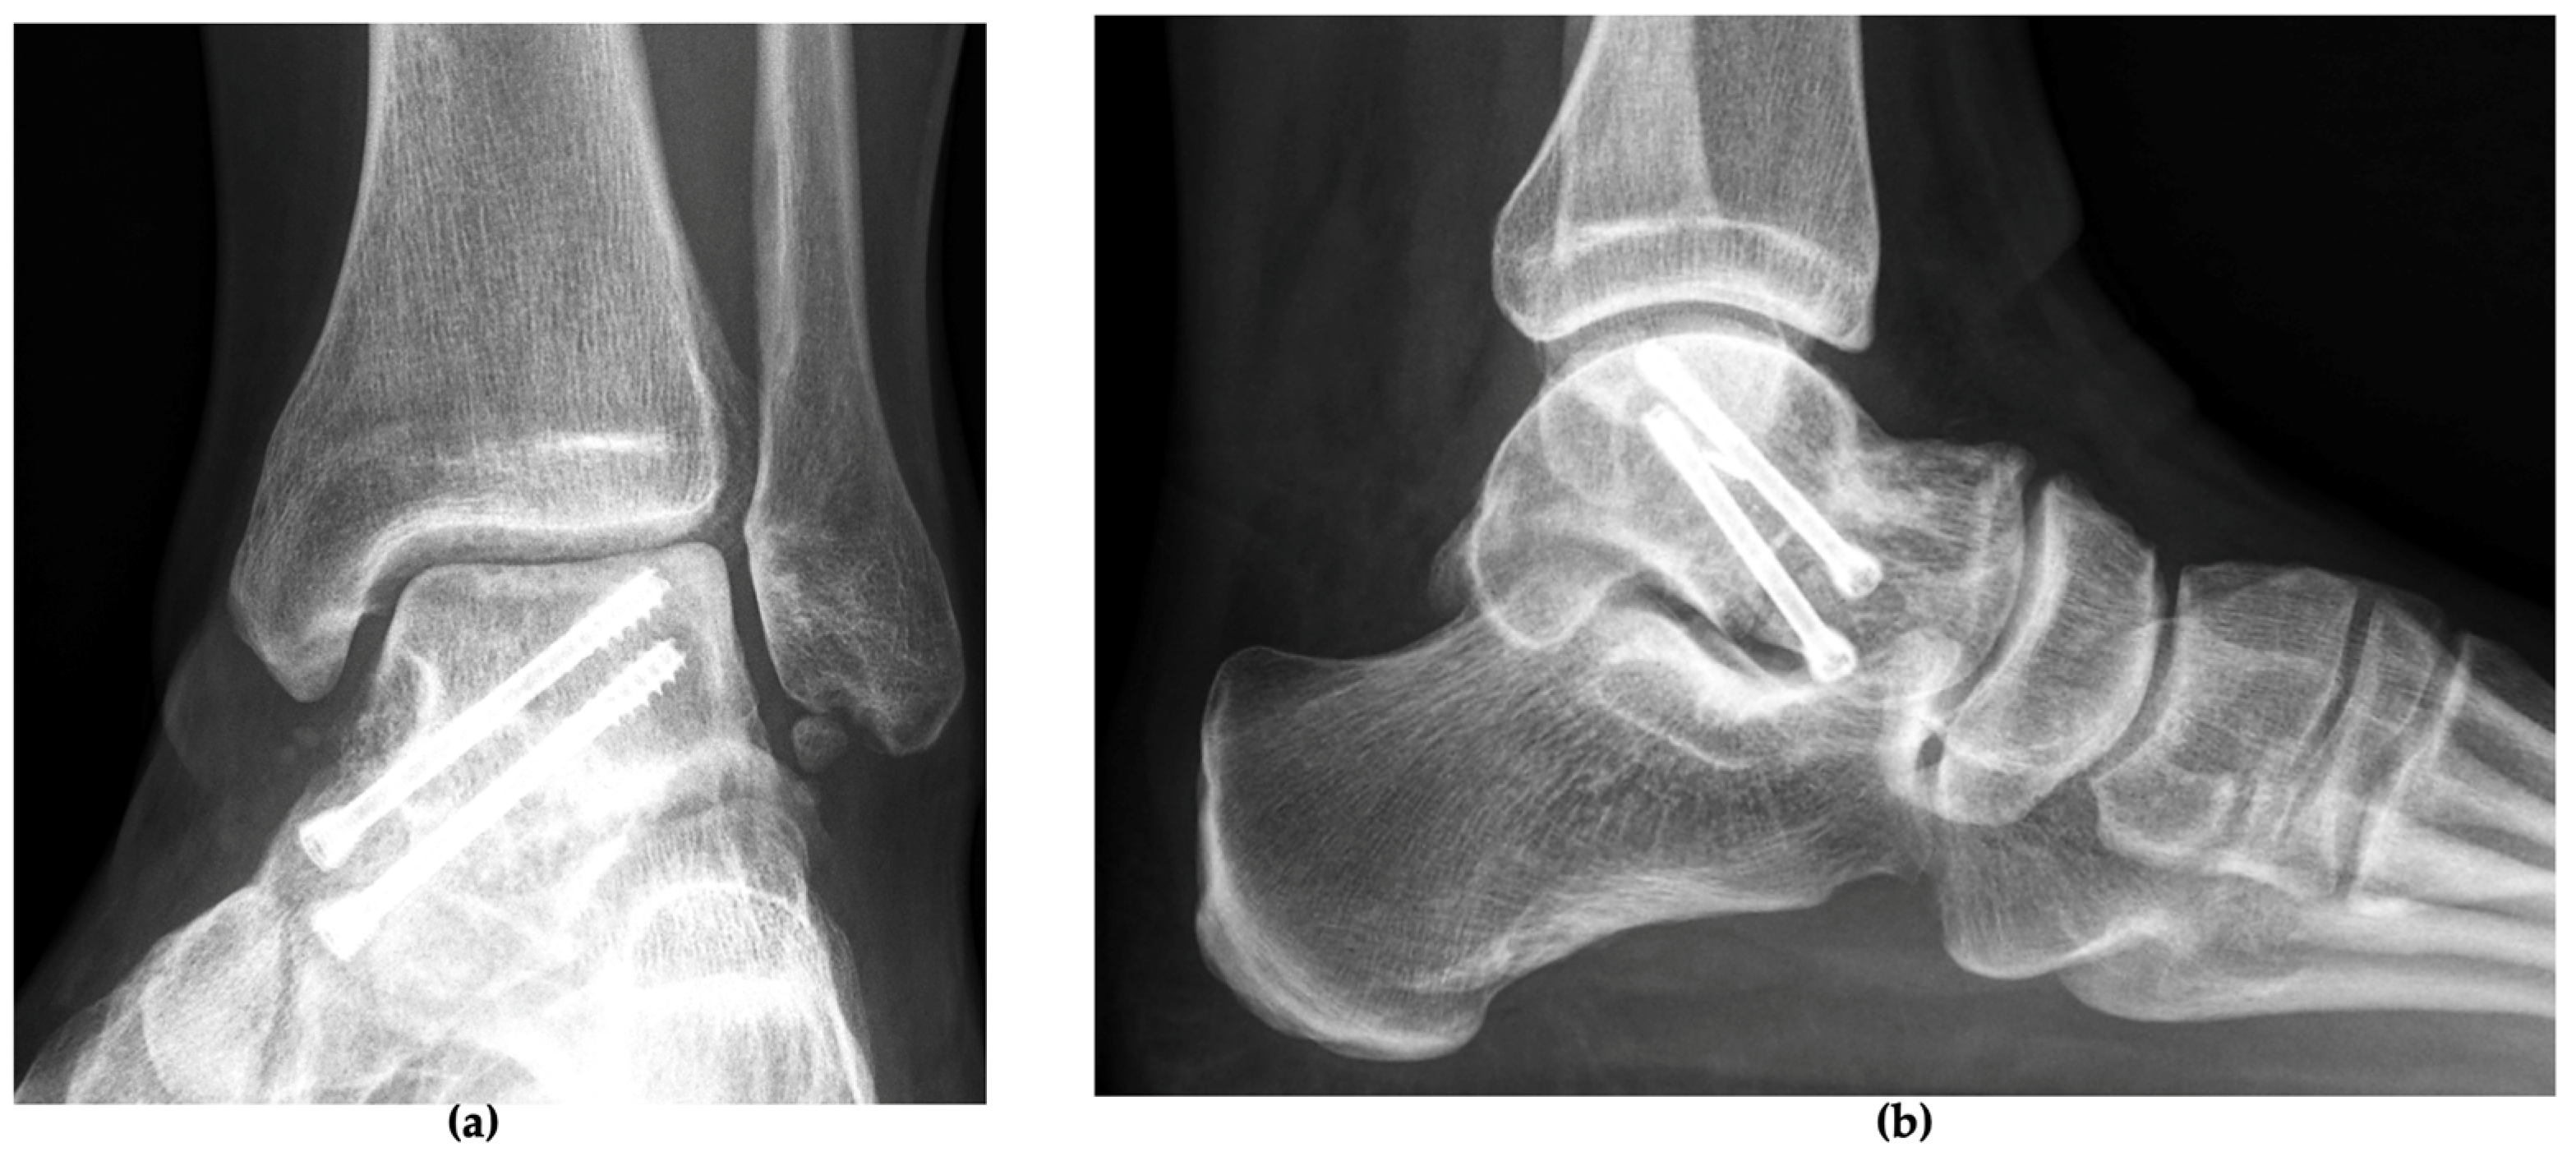

2.2. Therapeutic Intervention

3. Follow-Up and Outcomes